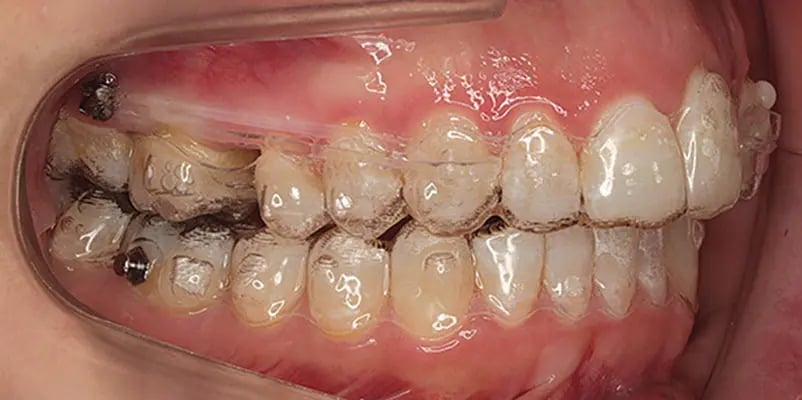

Molar distalization involves moving molars backward to create space for alignment or improve occlusion. This movement can inadvertently alter the vertical dimensions of the jaw, leading to unwanted changes like molar extrusion or open bites. Vertical control ensures the molars remain in the desired position vertically, maintaining harmony in the bite and facial aesthetics.

Aligners can minimize extrusion forces on molars, reducing the risk of open bites. Their snug fit and planned pressure distribution help maintain the vertical stability of teeth.Sequential Tooth Movement:

Strategically placed attachments can enhance the aligner's grip on molars, improving the precision of distalization and vertical control.

In cases where greater control is required, TADs are often used alongside aligners. These small, screw-like devices provide a stable anchor point, minimizing unintended movements during molar distalization. Here's how they contribute:

TADs prevent molar extrusion by anchoring adjacent teeth or structures, ensuring the molars only move distally.Skeletal Adjustments: